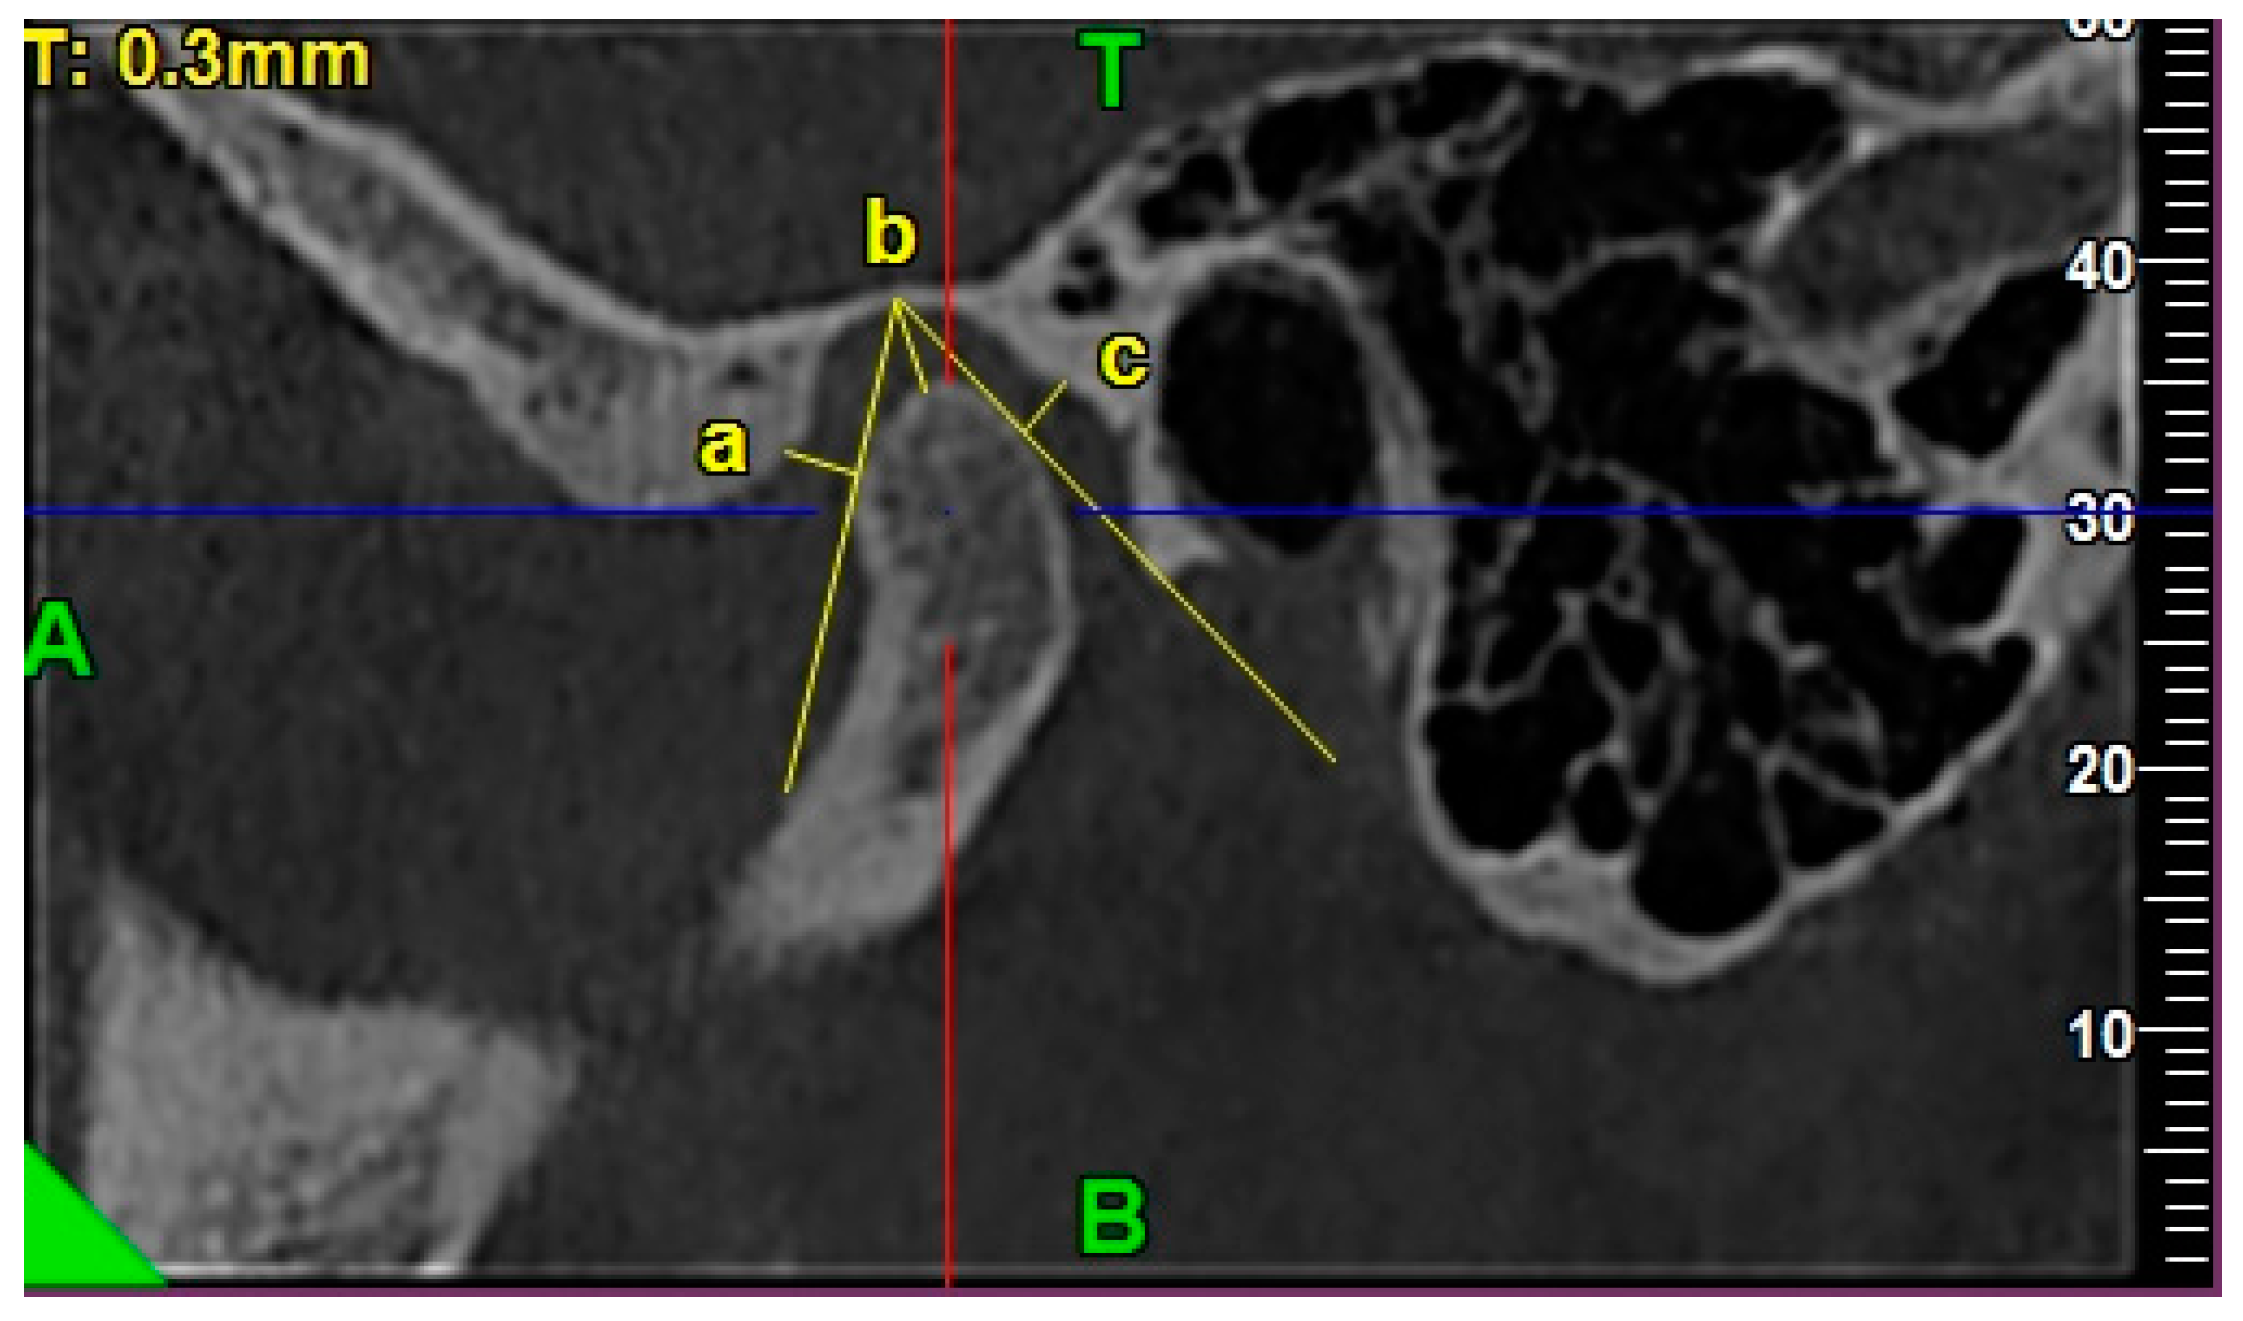

2.4.3. Morphology of the Articular Eminence

2.4.4. Assessment of the Anterior, Posterior, and Superior Joint Spaces

2.4.5. Assessment of the Sagittal Position of the Condyle

- P—posterior joint space,

- A—anterior joint space.